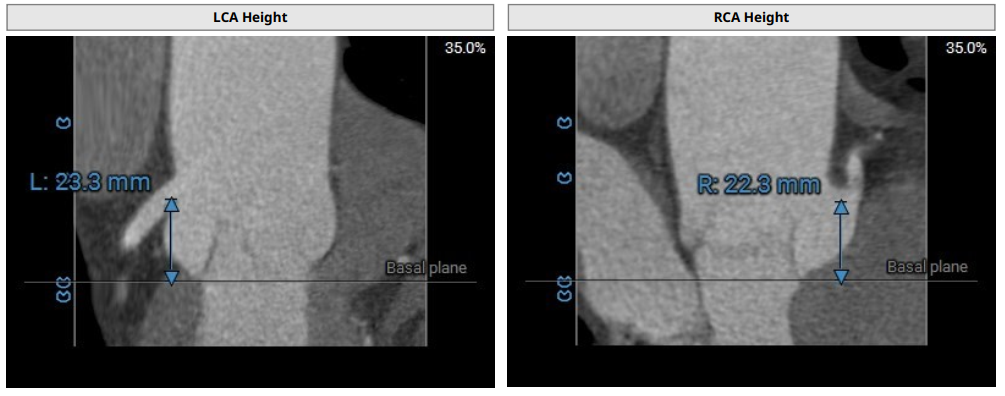

术前超声和DSA评估提示,患者三叶瓣结构,三个瓣窦,三窦偏大。主动脉瓣环30.1mm,左心室流出道直径28.1mm,STJ直径43.9mm,升主动脉直径47.4mm,左侧冠脉高度23.3mm,右侧冠脉高度22.3mm,左室-主动脉夹角132°。